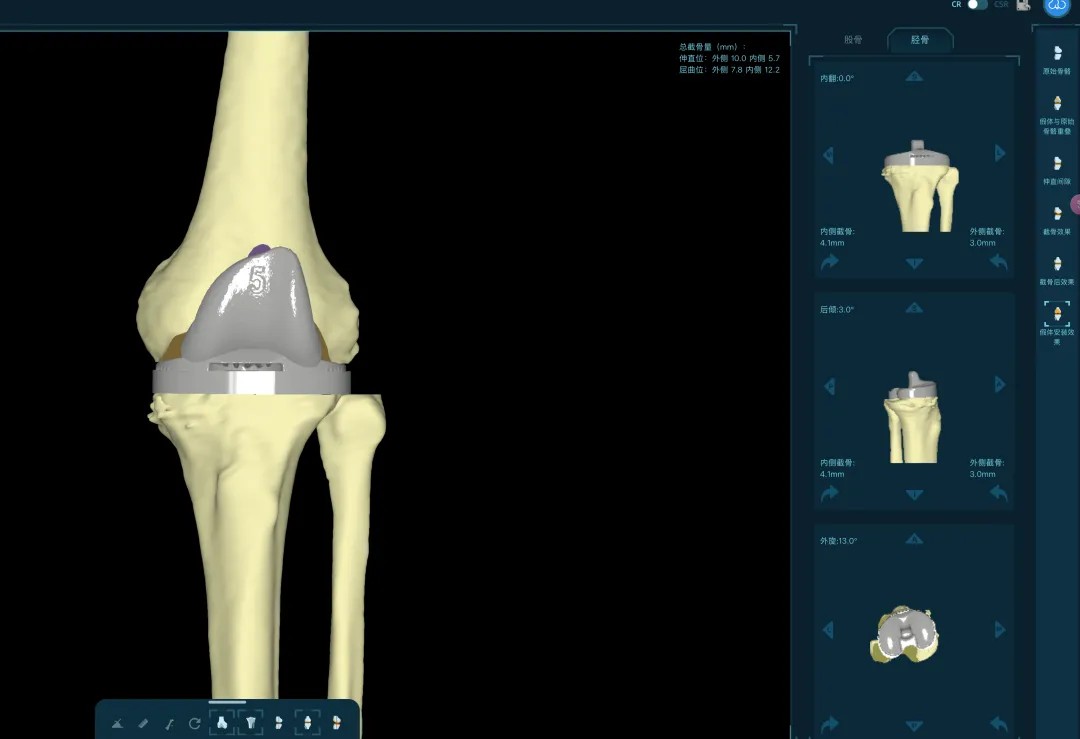

通过患者的CT数据,系统构建出膝关节的三维数字模型,精确评估骨缺损的范围与形态。医生可以在虚拟空间中,提前模拟手术过程,为患者“量体裁衣”,规划出假体安放的最佳位置、角度以及所需填充骨缺损的特殊垫块型号。

“这相当于在真实战斗前,进行了一次全方位的沙盘推演。”罗军介绍,这种规划确保了手术的精准度,缩短了手术时间,也为使用先进的翻修假体系统做好了完美铺垫。

本次手术的核心,是采用了Evolution® ECCK膝关节翻修系统。该系统专为应对翻修手术中常见的严重骨缺损、韧带功能不全等极端复杂情况而设计。

其模块化的组件提供了前所未有的灵活性,就像一套高精度的“工程套件”,允许医生在术中根据实际骨缺损情况,自由组合不同尺寸的垫块、延长杆等部件,实现关节线和力学稳定性的个体化重建。

尤为重要的是,该系统保留了内轴型假体的设计哲学,在重建关节稳定性的同时,努力模仿了人体膝关节自然的运动方式(内轴稳定性、外侧活动性),旨在让患者术后不仅能走,还能走得更舒适、更自然。